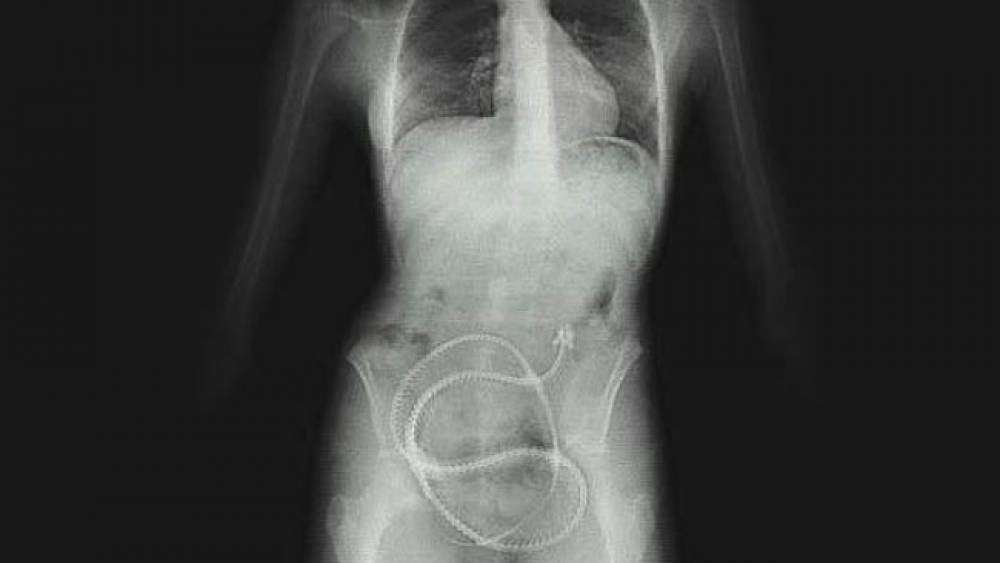

Se ha descubierto que en todas las patologías está presente “la enfermedad de la Tenias”. Los estadios producen huevos. Estos expulsan sus pequeñas larvas y quistes, juntos con los huevos no fecundados y sus bacterias en todo el cuerpo haciendo que la persona se sienta muy enferma. Puede ser que la gran cantidad de solventes acumuladas en el cuerpo, los haga idóneos para la empolladura; o puede ser que la baja protección inmunológica le permite producir huevos. Estudios recientes en enfermedades severas, revela las cabezas (scolex) y huevos en casi todos los órganos vitales: el timo, el bazo, la médula espinal, el cerebro y el hígado. Las fases de Tenias no llegan solas. Llevan consigo bacterias y virus nocivos. Streptomyces fungus es uno de los peores. Siempre se encuentran en la cercanía de un Streptomyces, dondequiera que esté.

Por otra parte las ascárides infectan los animales y los humanos desde un extremo hasta el otro de la tierra. Se puede predecir con cierta exactitud que todos los perros y los gatos tienen ascárides, como también ciertas personas. Las personas y los animales domésticos tienen cierto tipo de ascárides, pero pueden hospedar un tipo diferente. Los caballos tienen la ascáride megalocéfala. Los puercos tienen ascárides suum. El tipo que infecta las personas es el lombricoide. Las ascárides no atacan el cuerpo. Casi no se mueven. Permanecen inmóviles en el cuerpo, usando sustancias nutritivas y llenándose de huevos. Si combatimos los gusanos de las ascárides con recetas de hierbas, los herimos mortalmente. Ellos mueren, pero no sus huevos. Los huevos son protegidos. En el lapso de un día estos huevos dejan el gusano moribundo y después de poco tiempo miles de ellos andan por todo el cuerpo. En 24 horas se transforman en larvas.

Estos no son unos intrusos comunes, aunque los encontramos dondequiera en la suciedad. No se podrá mejorar la salud si no se puede eliminar cada grano de Hydatider Sand y otras larvas que quedan en el cuerpo.